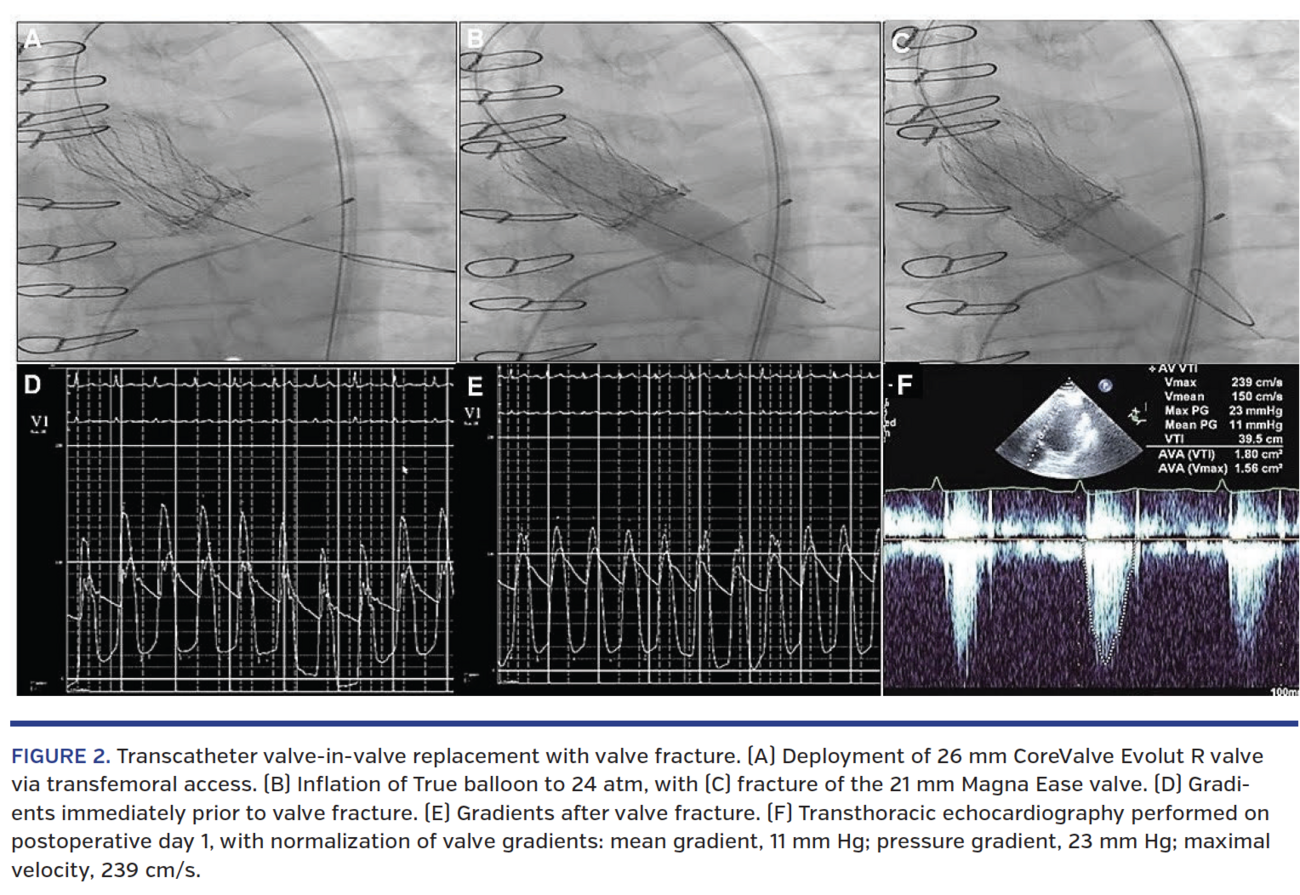

Standard techniques for TAVR2 and BVF2,3 were employed. Access was obtained in the left femoral artery and vein without complication, and a temporary pacing wire was placed from the right femoral vein. A 6 Fr pigtail catheter was then advanced from the left femoral artery to the ascending aorta. At the right femoral artery, percutaneous access was obtained, Perclose sutures (Abbott Vascular) were placed, and a placeholder 14 Fr sheath was placed in the right femoral artery. The aortic valve was then crossed in a retrograde fashion using a straight wire and diagnostic 6 Fr AL1 catheter. Simultaneous LV and aortic (Ao) pressures were recorded, and noted to be 140/15 mm Hg (LV) and 90/62 mm Hg (Ao).The pigtail was then removed from the ventricle over a stiff exchange wire and the 16 Fr sheath was exchanged over the wire for the 16 Fr inline sheath. A 26 mm Evolut R valve was placed without complication. The valve was carefully placed to ensure optimal placement with high implant to optimize hemodynamics and the valve was deployed with slow ventricular pacing (Figure 2A).

Intraprocedural TTE performed after valve deployment showed no aortic insufficiency or paravalvular leak and good function. Mean gradients had improved from 52 mm Hg to 24 mm Hg after valve implant; Vmax was 300 cm/s. Given normal leaflet motion in the surgical valve, improved gradients were likely attributable to supra-annular position of the self-expanding TAVR valve. As planned, BVF of the 21 mm Magna Ease bioprosthetic valve was performed with a 22 mm True balloon (C.R. Bard; Figure 2B) with a tactile, audible, and visible fracture of the valve (Figure 2C). Post-BVF mean gradients were assessed and noted to be 5 mm Hg by catheter (Figure 2D) and 9 mm Hg by echocardiography (Figure 2E). Given this result, the procedure was considered successful. The stent-valve delivery system was then removed over the wire. The large sheath was removed from the right and the two Perclose sutures were deployed. The patient was then taken to the postoperative recovery area, where he emerged from sedation without complications and recovered overnight in the cardiac surgery intensive care unit (ICU).

On postoperative day 1, he was transferred out of the ICU, with repeat TTE showing mean gradients stable at 11 mm Hg. He remained hemodynamically stable, and was ambulating without chest pain, shortness of breath, weakness, or fatigue. At his 30-day follow-up as an outpatient, he remained symptom free, with repeat TTE showing ejection fraction of 70%, mean gradient of 13 mm Hg, pressure gradient of 26 mm Hg, and Vmax of 257 cm/s. He had also returned to work full time, and reported continued absence of symptoms at rest and with exertion.